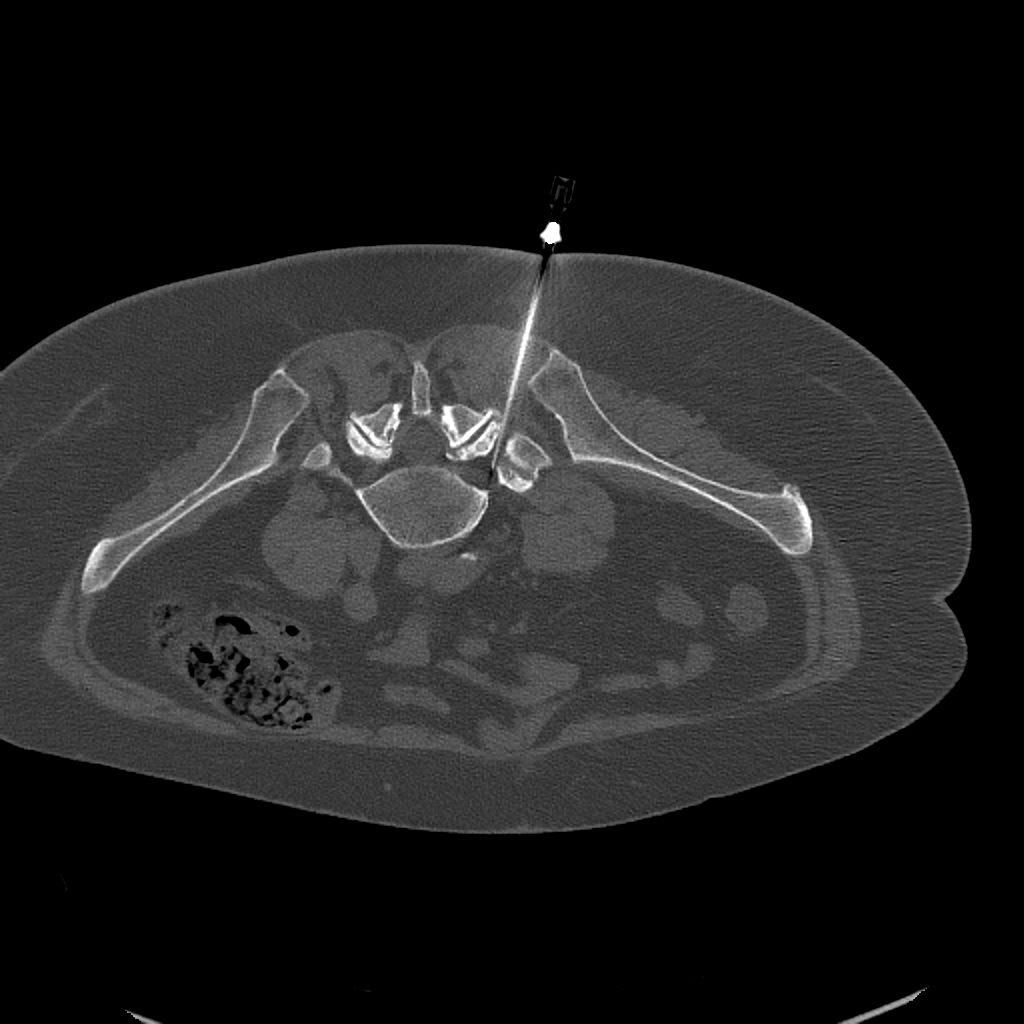

CT-Guided Targeted Block

Targeted block injection is one of the most effective tools in the conservative management of spinal pain. There are two main types, depending on whether the nerve root or the facet joint is the source of symptoms.

CT-vezérelt ideggyöki blokád — axiális CT-felvétel a tű pozíciójával

CT-guided nerve root block: the image clearly shows precise needle positioning next to the affected nerve root

Nerve Root Block

When the exiting nerve root is the source of pain — for instance due to disc herniation or spinal stenosis — targeted nerve root block injection therapy is indicated. During the procedure, a minimal amount of local anaesthetic and anti-inflammatory steroid is delivered next to the affected nerve root.

Needle positioning is verified by CT or fluoroscopy to ensure only the inflamed nerves are treated. Temporary numbness or weakness may occur due to the anaesthetic — this is a normal phenomenon that typically resolves within a few hours.